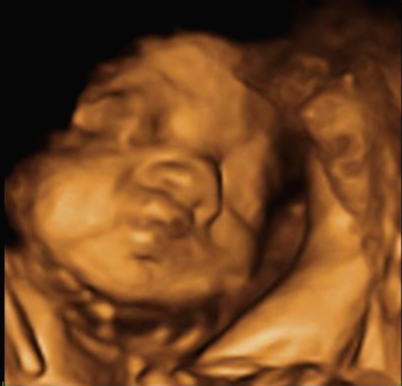

24주 차에 다시 사설로 초음파 검사를 받으러 갔는데 초음파를 보시더니 정밀 초음파 검사 때 성별 딸이 었냐 아들이 었냐 물어보시길래 딸이라고 말을 하니 미안하다고 지금 보니 딸이라고 하길래 이때는 정밀 초음파 검사 후 한 달 뒤여서 상관없다고 ㅋㅋㅋㅋㅋ 아들인지 딸인지 뭐가 중요하냐고 아이만 건강하면 된다고 하니 ㅎㅎ 그때서야 웃으시더라고요 ㅎㅎ 많이 미안했던 모양... 워낙 아이 건강상태를 꼼꼼하게 잘 봐주시고 만족할만하게 아이 얼굴 초음파 사진을 찍어주셔서 다 용서가 됐어요 ㅎㅎ

내 뱃속에 이렇게 사랑스러운 아이가 있다니 >. < 이렇게 이쁜 아이를 보면 성별반전은 중요하지 않아요~

입체 초음파 사진은 항상 만족스러워요! 사진 보면 벌써 태어난 아기처럼 어찌 이리 이목구비 뚜렷하고 아이 얼굴이 선명하게 잘 보이는지~ 제아이라 이렇게 사랑스러운 걸까요~? ㅋㅋㅋ